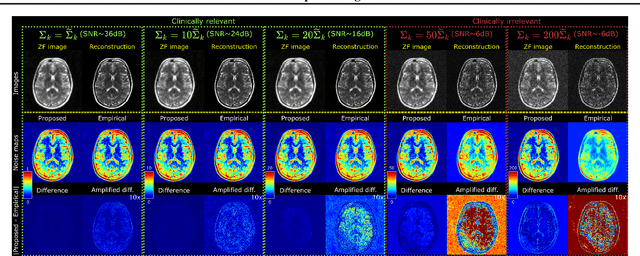

Abstract:Accelerated MRI reconstruction involves solving an ill-posed inverse problem where noise in acquired data propagates to the reconstructed images. Noise analyses are central to MRI reconstruction for providing an explicit measure of solution fidelity and for guiding the design and deployment of novel reconstruction methods. However, deep learning (DL)-based reconstruction methods have often overlooked noise propagation due to inherent analytical and computational challenges, despite its critical importance. This work proposes a theoretically grounded, memory-efficient technique to calculate voxel-wise variance for quantifying uncertainty due to acquisition noise in accelerated MRI reconstructions. Our approach approximates noise covariance using the DL network's Jacobian, which is intractable to calculate. To circumvent this, we derive an unbiased estimator for the diagonal of this covariance matrix (voxel-wise variance) and introduce a Jacobian sketching technique to efficiently implement it. We evaluate our method on knee and brain MRI datasets for both data- and physics-driven networks trained in supervised and unsupervised manners. Compared to empirical references obtained via Monte Carlo simulations, our technique achieves near-equivalent performance while reducing computational and memory demands by an order of magnitude or more. Furthermore, our method is robust across varying input noise levels, acceleration factors, and diverse undersampling schemes, highlighting its broad applicability. Our work reintroduces accurate and efficient noise analysis as a central tenet of reconstruction algorithms, holding promise to reshape how we evaluate and deploy DL-based MRI. Our code will be made publicly available upon acceptance.